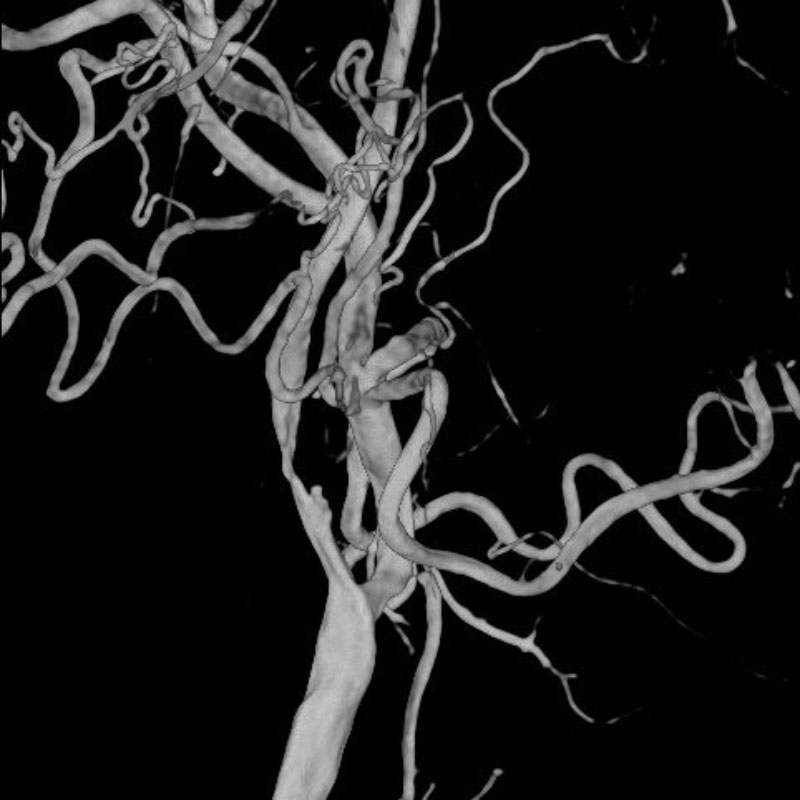

脳動静脈奇形

血管塞栓術

松田/濵田/元永